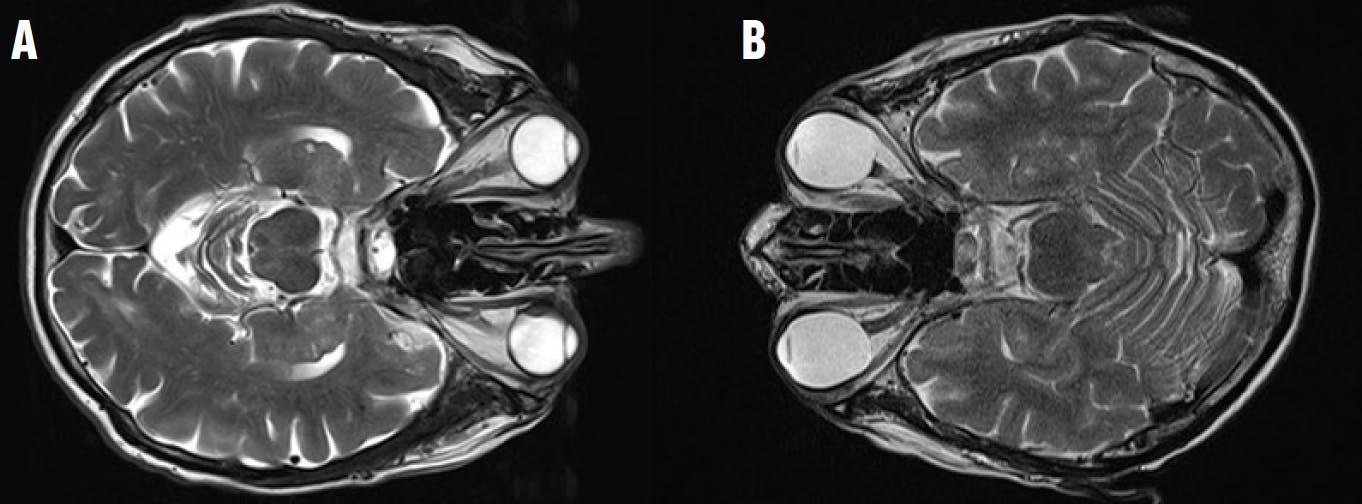

<p>Figure 1. MRI shows the shapes of hyperopic (A) and myopic (B) eyes.</p>

Figure 1. MRI shows the shapes of hyperopic (A) and myopic (B) eyes.

Based on the volume of a sphere with the diameter of the AL, which shows a volume of AL³ x π/6, a correction factor of 0.76 + 0.012 x (AL-24) was derived to account for the portion of the vitreous in the entire globe and the proportional increase of the vitreous for long (ie, myopic) eyes. This correction was developed based on the MRI analysis of emmetropic, myopic, and hypermetropic eyes (Figure 1).